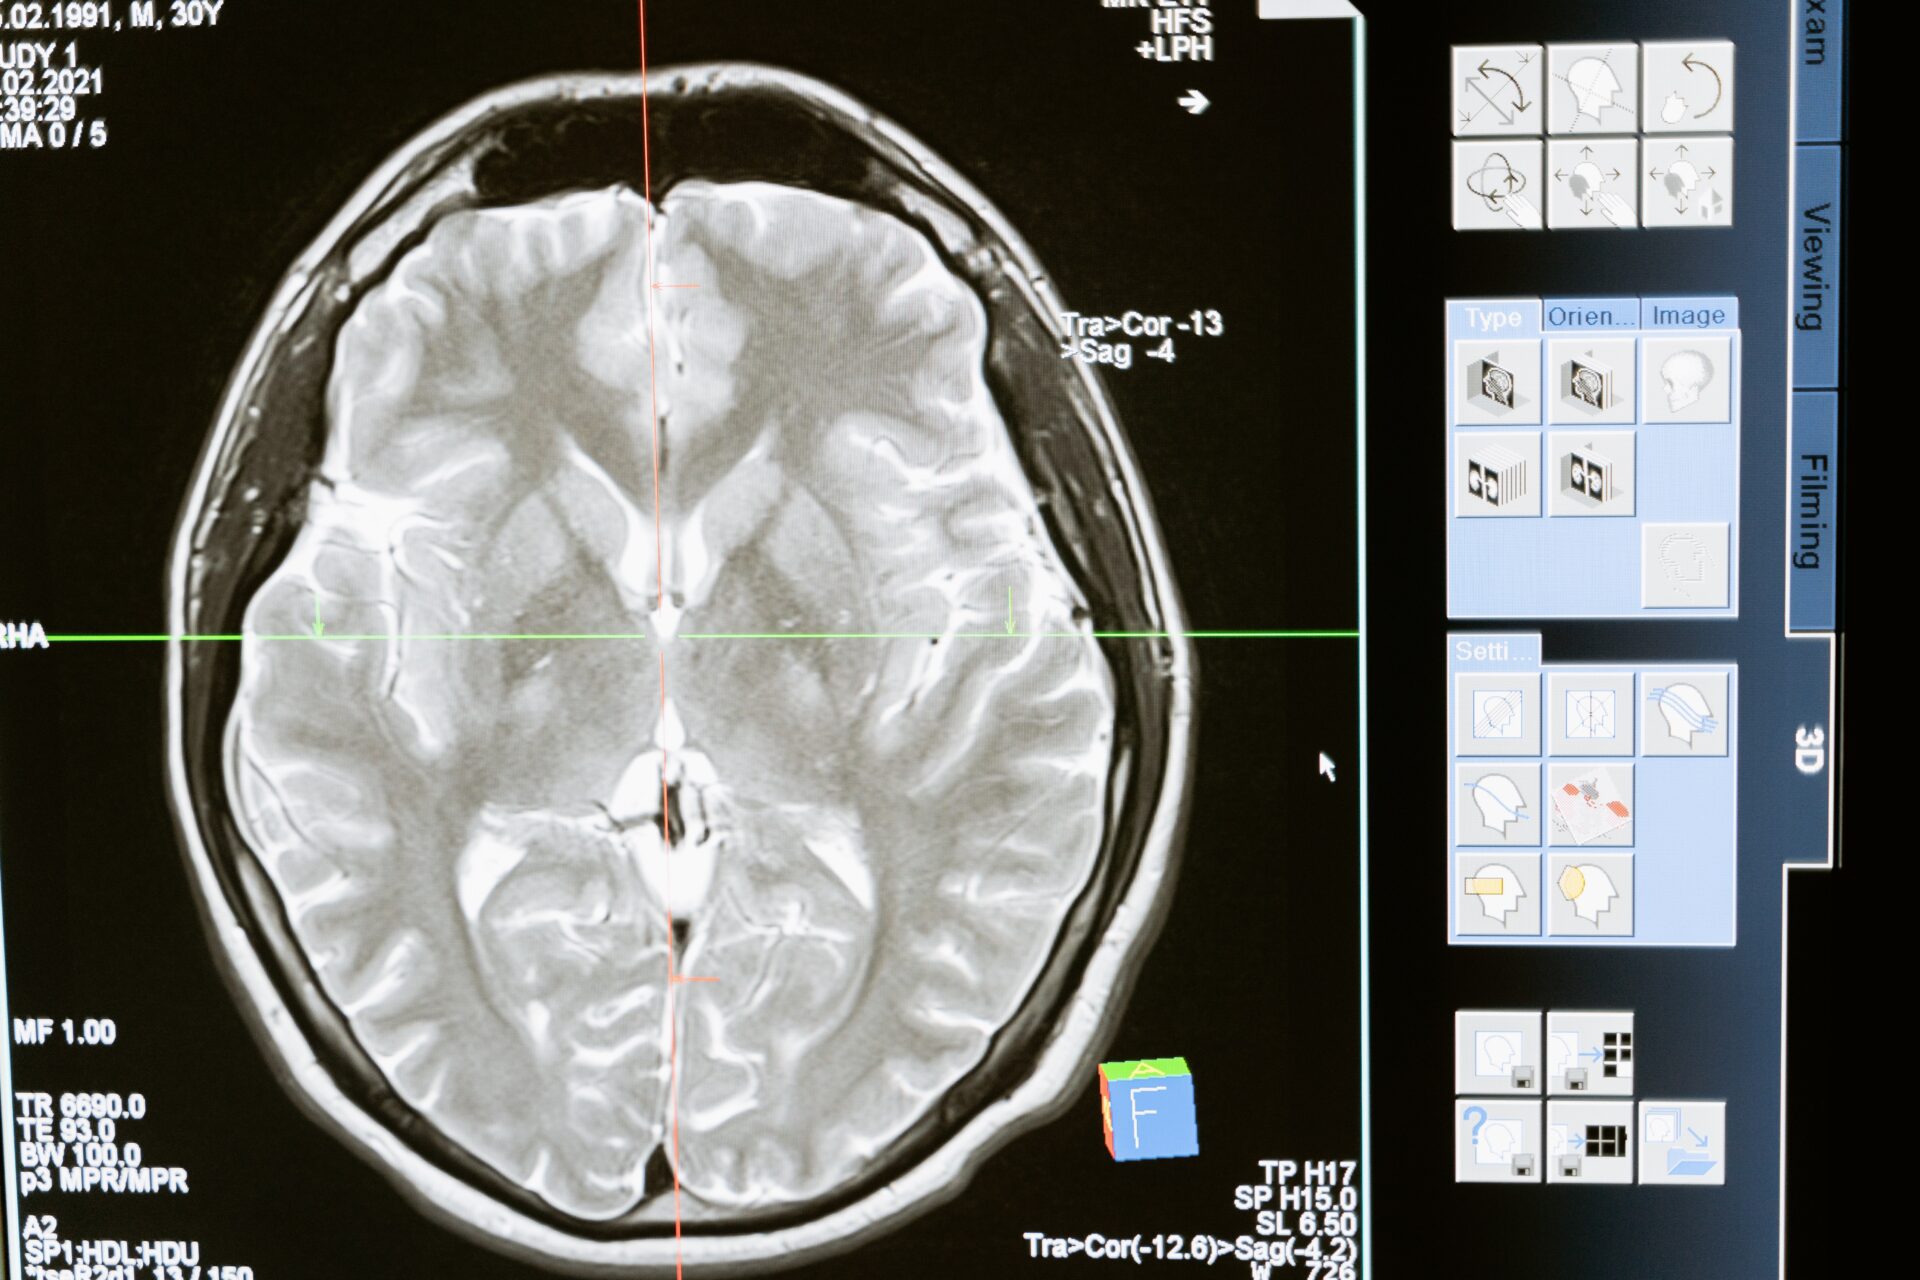

Om de werking van het menselijk brein te begrijpen, moeten onderzoekers accepteren dat een begrip van iets dat zo complex is niet kan worden bereikt door kleinschalige experimenten waarbij individuele uitkomsten afzonderlijk worden bekeken. Daarnaast moeten ze de mogelijkheden omarmen die kunstmatige intelligentie en machineleren kunnen bieden. Dat is de oproep die psycholoog Lukas Snoek doet in zijn promotieonderzoek Towards prediction: Studying the mind and brain in the age of machine learning. Hij verdedigt zijn proefschrift op woensdag 9 februari aan de Universiteit van Amsterdam (UvA).